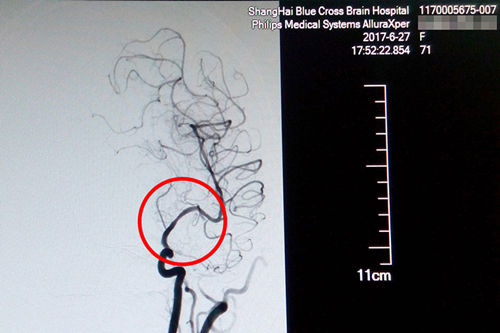

术后DSA影像显示,患者血管狭窄部位血流恢复正常

站在手术台前的李主任,表现出的是与平日不同的冷静和沉着。经术中精准测量发现,患者盛阿姨血管狭窄达到了77%,血管非常狭窄,使放置球囊扩张支架的难度更大。好在李主任积累了丰富的DSA手术经验,经过仔细小心的操作,导丝成功地通过了狭窄的血管。李主任用他的“血管艺术”使濒临枯萎的血管重新绽放出了生命的活力,最终原本非常狭窄的血管腔顺利张开了:“……将球囊扩张支架置入狭窄处,观察后准确释放球囊扩张支架,再造行3D造影,显示血管扩张,血流恢复正常。(摘自术后小结)”。